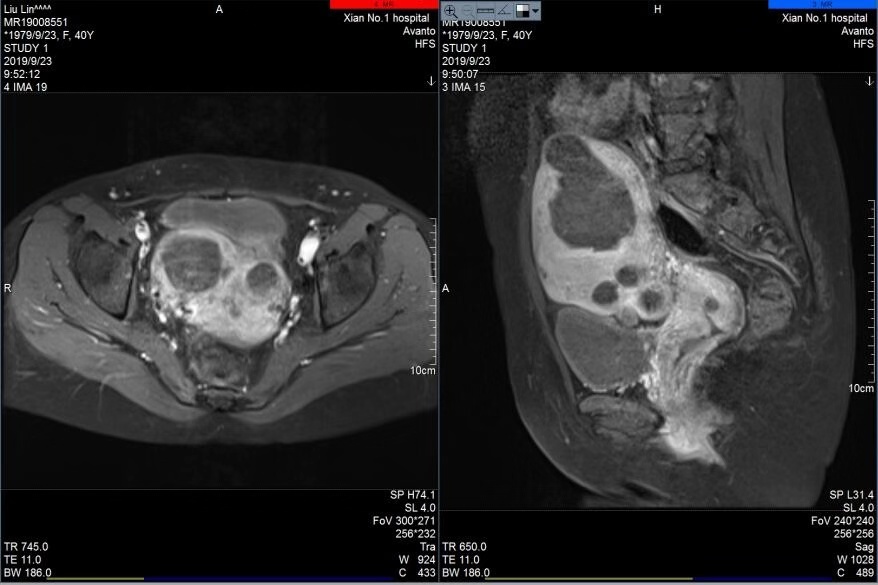

宋迎春主任在海扶刀治疗中心通过对其肌瘤进行上机定位与评估,患者完善了各项入院检查与胃肠道准备后,于2019年9月20日对其肌瘤进行海扶消融治疗,术中只用了752秒的辐照时间,就成功消融了7个肌瘤和1个腺肌瘤病灶,瘤体最大者近7cm,最小肌瘤约1cm,术前术后超声造影显示肌瘤大范围消融坏死,手术达到预期效果,患者十分满意。